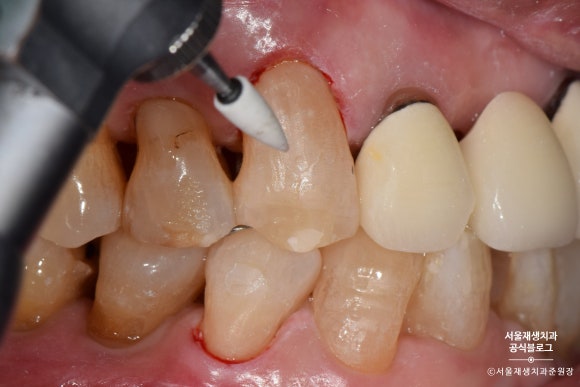

들뜬 자리가 없도록 꼼꼼하게 레진을 다듬어줍니다.

사진상으로는 모두 나오지 않지만,

반질반질하고 심미적인 결과를 위해서

여러번의 마무리 과정을 거치게 됩니다.

짠!

완성되었습니다.

치아와 잇몸의 경계부위를 때우기 때문에,

깔끔한 마무리를 위해 잇몸쪽으로 기구 손질을 많이 하게 됩니다.

잇몸 가장자리가 빨개진 것은 대개 하루이틀이면 원래대로 돌아옵니다.

꼼꼼한 치료의 결과라고 생각해주시면 됩니다^^